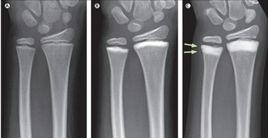

出生時,骨骼X線檢查通常正常,隨著兒童期的進程,骨骼硬化逐漸變得明顯.骨骼受累廣泛但呈斑點狀,肢體末端有骨質疏鬆.顱頂骨緻密,副鼻竇閉塞.脊柱椎骨終板硬化隆起出現"橄欖球運動衫"樣形狀.某些患者需要輸血或脾切除術治療貧血.